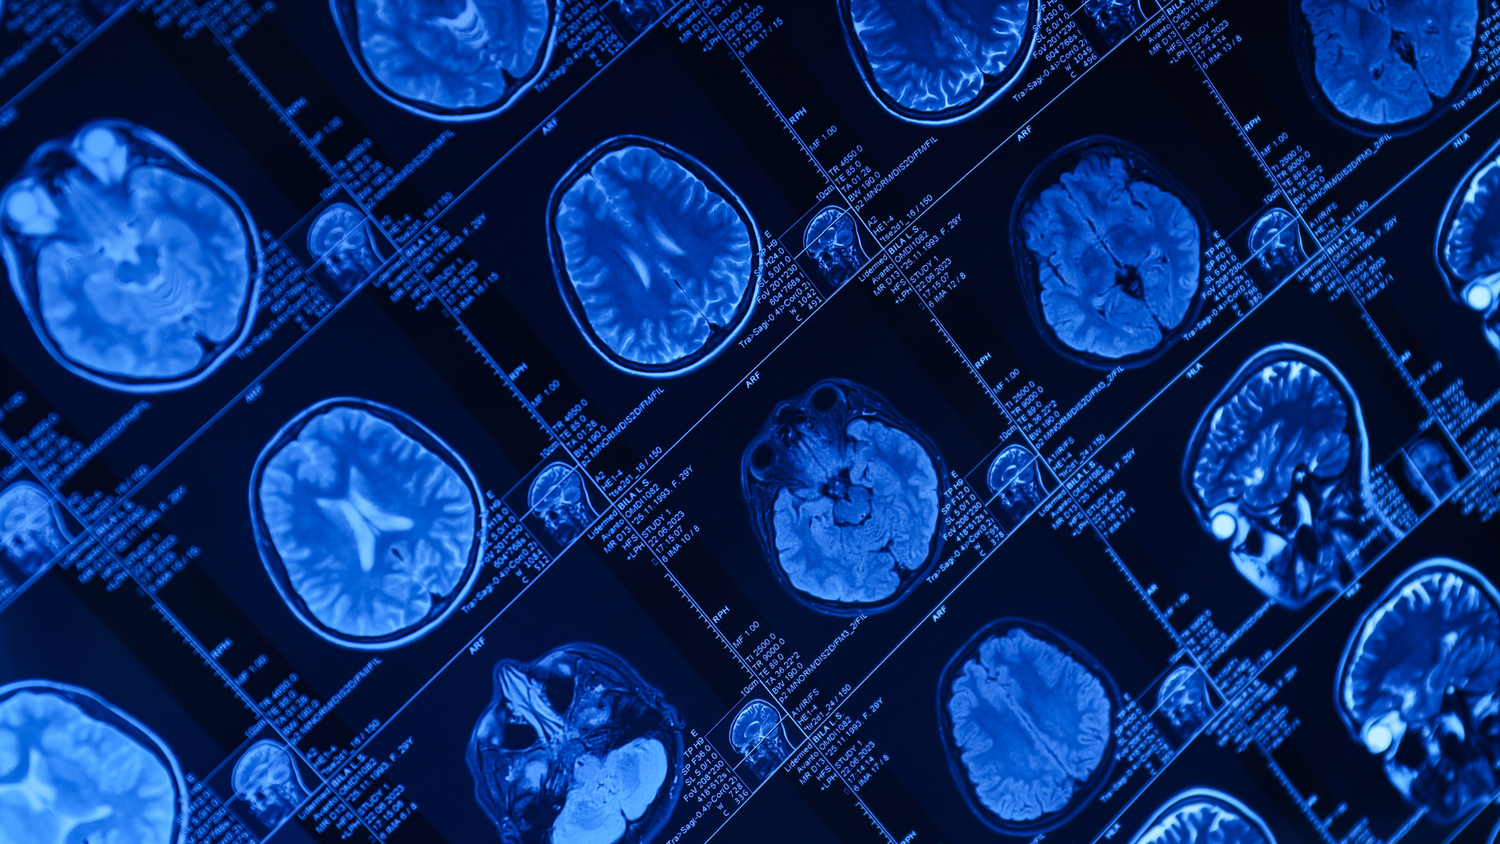

Maintaining brain health is crucial for overall well-being and cognitive function. As we age, the risk of neurodegenerative diseases increases, making it essential to find effective ways to support brain health. Methylene blue, a compound with a long history in medical use, has shown promising results in enhancing brain health. This blog explores what studies reveal about methylene blue and its impact on brain health.